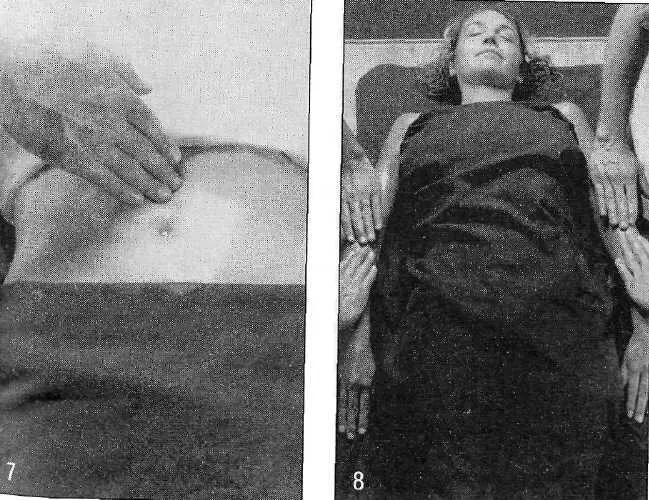

Бахья снехана представляет собой последовательность массажных движений, выполняемых в следующих направлениях: от пупка к голове, от головы к пупку, от пупка к ногам и от ног к пупку — на передней и задней поверхностях тела. Давление, прилагаемое массажистом, различается в зависимости от массируемой области (присутствия точек мармы). Согласно аюрведе, в точках мармы происходит соединение между физической материей тела и его внутренней мудростью. Стимуляция мармы оживляет и координирует взаимодействие субдош ваты, а следовательно, гармонизирует все нейрофизиологические процессы в организме.

Массаж и травы позволяют маслу проникать глубоко в ткани и разрыхлять «укладку» амы в этих тканях, в том числе на стенках шрот. Помимо этого, снехана увеличивает гибкость тела, увеличивает силу, уменьшает стресс и питает ткани. Слово «снехана» буквально означает «доброта, нежность, любовь», и эта приятная процедура оправдывает свое название.

Чтобы подготовиться к главным очистительным процедурам, пациент получает внутреннее и внешнее промасливание ежедневно в течение семи дней. Такое время требуется маслянистым субстанциям, чтобы достигнуть всех семи дхату. После седьмого дня масло перестает впитываться и положительный эффект промасливания сменяется на противоположный. В случае дальнейшего продолжения процедуры масло стало бы накапливаться в виде насыщенных жиров, привело бы к ослаблению агни дхату, блокировке шрот и нарушению движения ваты. Побочным эффектом слишком длительного промасливания бывает плохое удаление мал, твердый стул и вздутие живота. По этой причине на восьмой день всегда начинают основные очистительные процедуры панчакармы.

Существуют классические признаки того, что снехана приблизилась к завершению, то есть масло пропитало все семь дхату. Кожа становится мягкой, блестящей и слегка пахнет маслом. Мягкие волосы. Выделительные процессы здоровые, фекальные массы желтоватые, блестящие либо маслянистые и мягче, чем обычно. Моча и испражнения пахнут ги. Моча ярче по цвету, чем обычно. Секреты слезных желез, выделения из носа и ушей слегка блестят. Нарастает сила, энтузиазм, энергия и ясность ума.